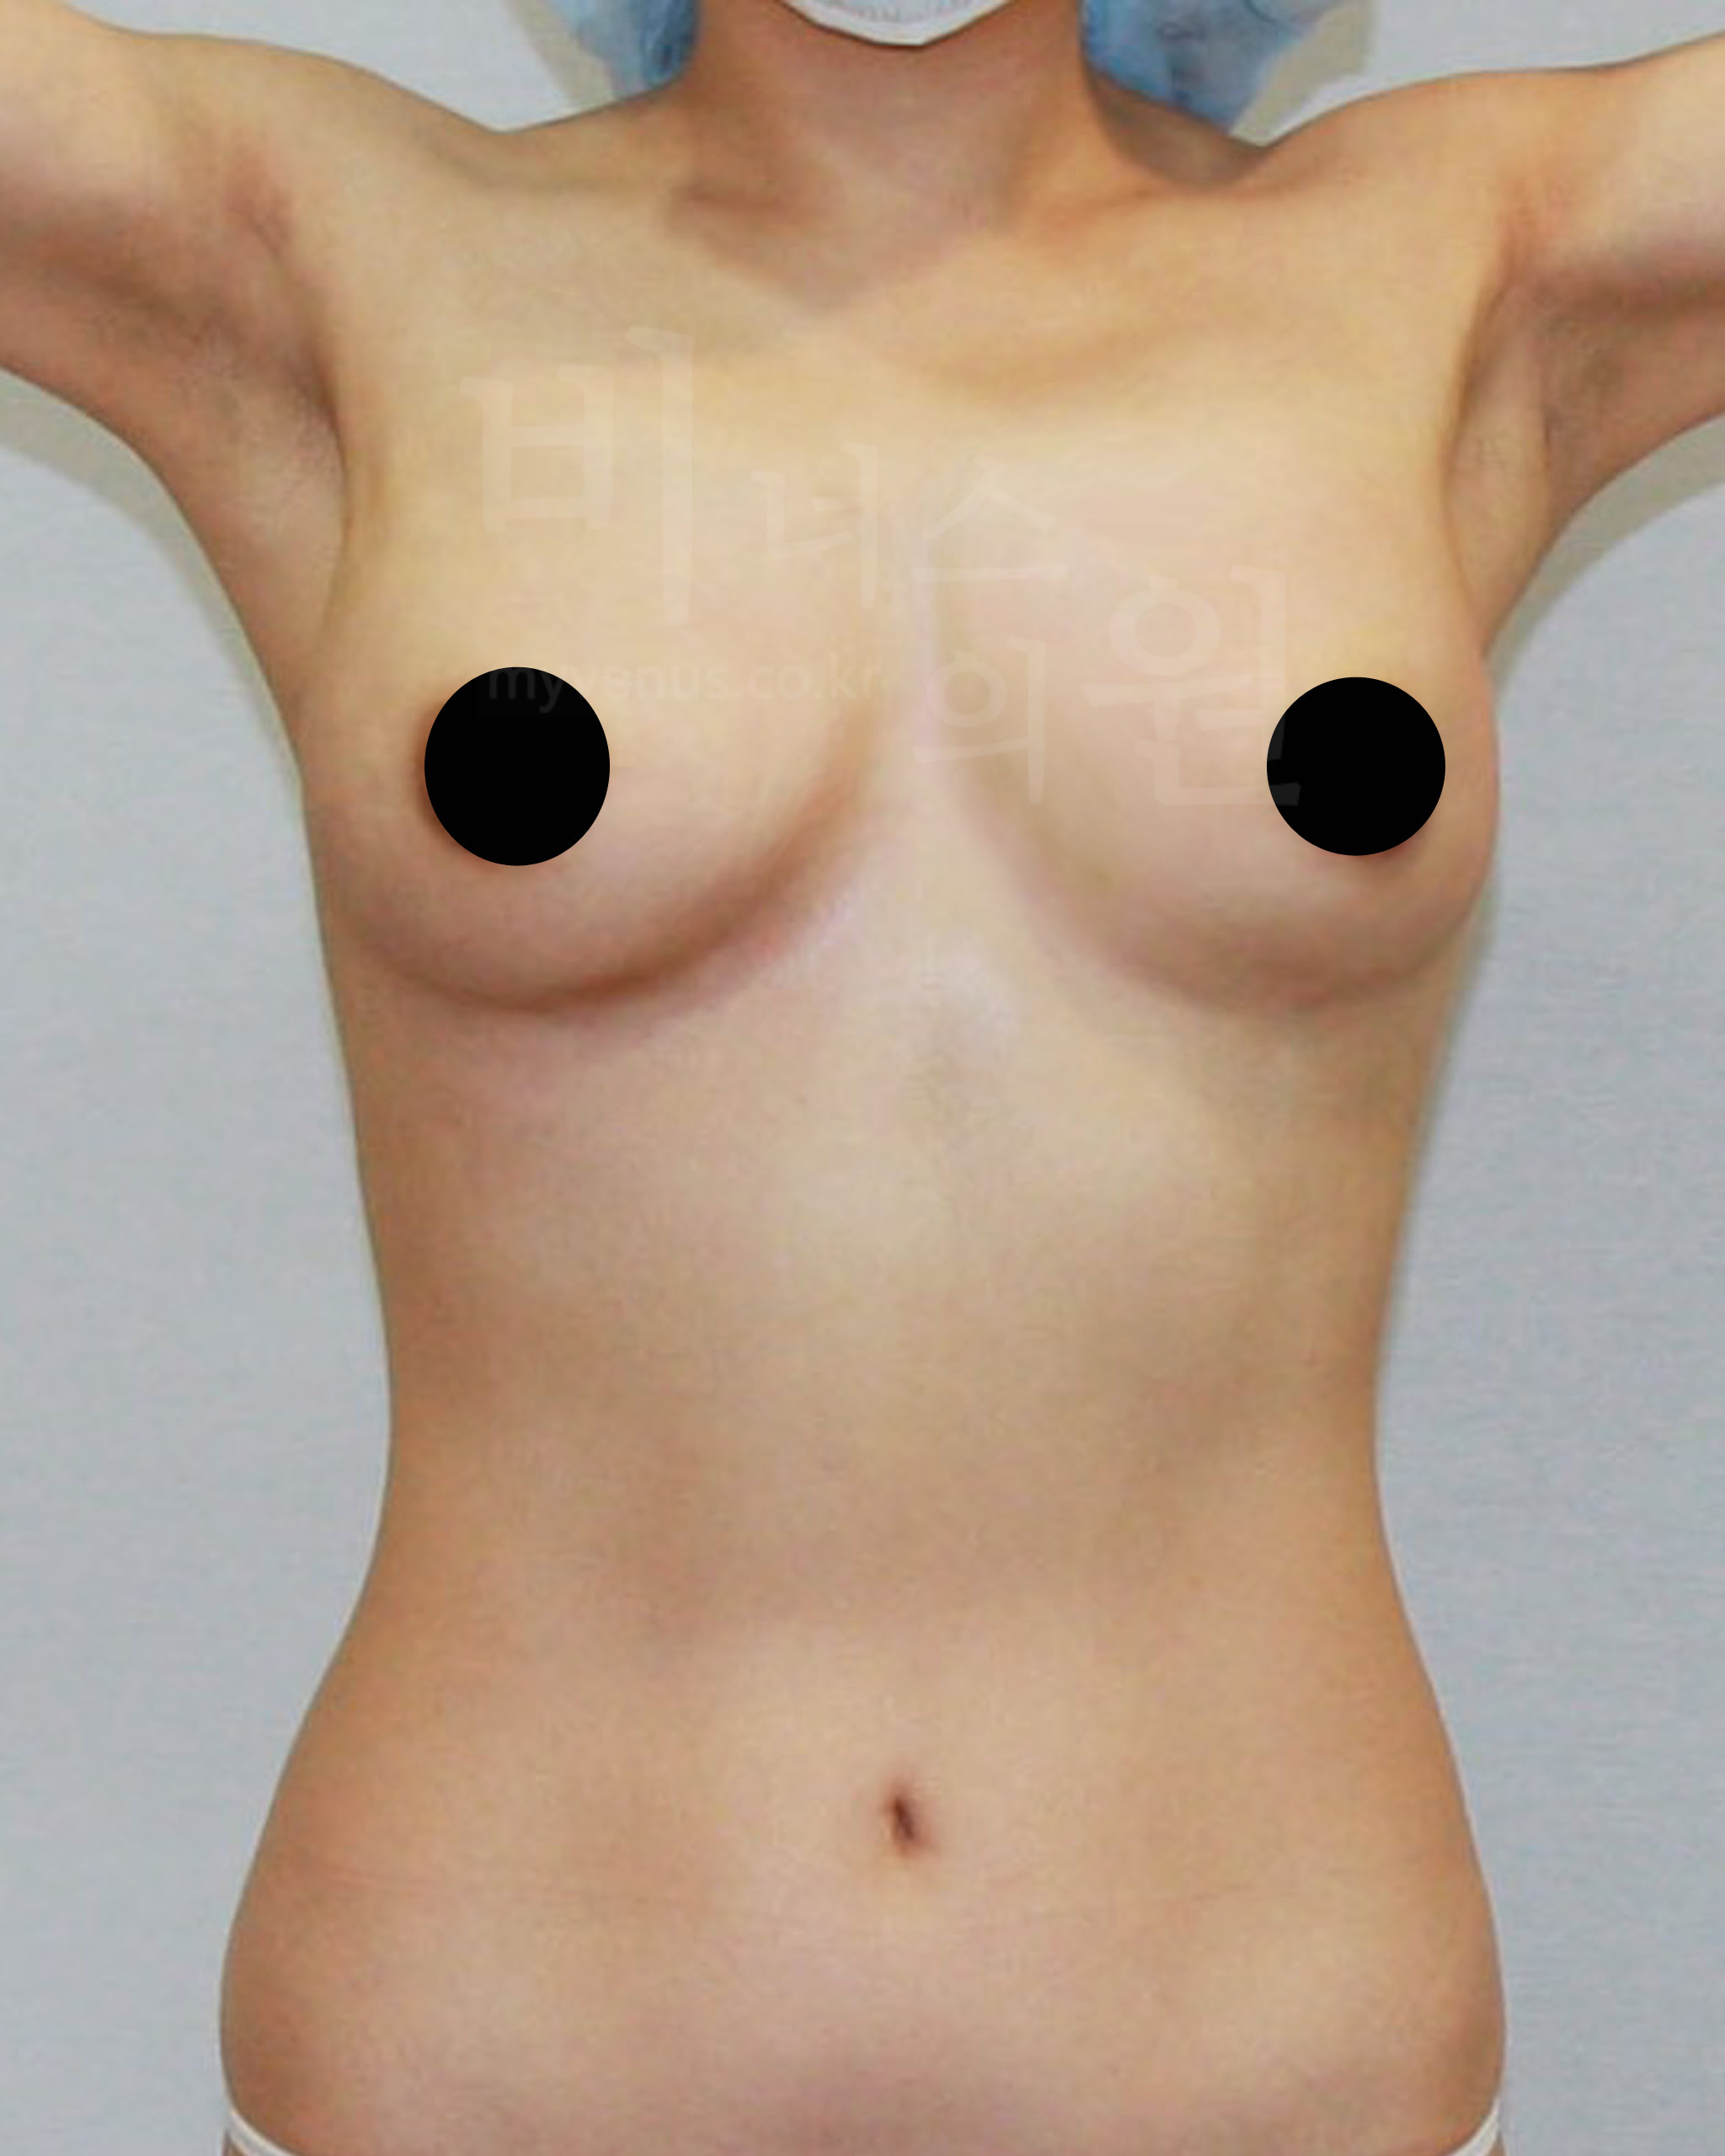

가슴축소 지방흡입 전 사진

탄력이 없어 힘 없이 가슴이 아래로 향한 모습

가슴축소 지방흡입 후 사진

피부 수축으로 리프팅과 탄력이 생긴 모습

가슴축 지방흡입은 절개를 하지 않아도 충분히 사이즈 감소와 처짐 없이 볼륨 업된 가슴으로 교정이 가능해요. 또한 유선을 건드리지 않고 지방만을 흡입하여 축소하기 때문에 젊은 여성분의 추후 모유수유에도 지장이 없어요. 멍, 붓기, 흉터, 부작용의 발생 없이 가슴이 자연스러운 모양으로 감소된 모습이에요.